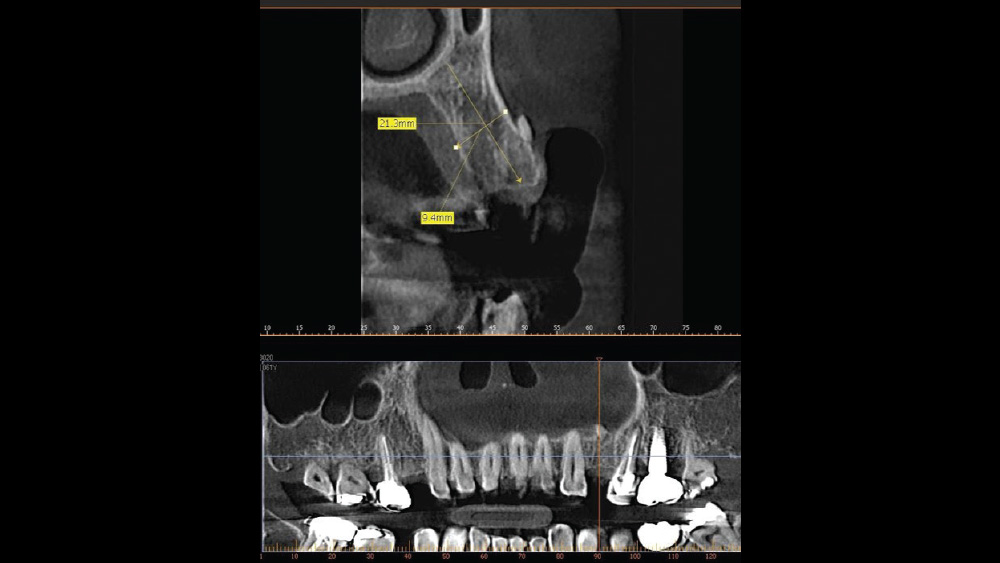

After gaining a clear understanding of the available hard and soft tissue through intraoral evaluation, radiography and — when possible — CBCT scanning, the clinician can determine whether flap reflection or a flapless surgical procedure is ideal for the individual patient. Both of these surgical techniques offer advantages, and the approach should be determined based on the amount of attached tissue present at the implant site, as well as the volume of bone.

The following case, which I performed alongside Dr. Stephanie Tilley of Pensacola, Florida, illustrates the use of both surgical techniques for the same patient, who presented with edentulous spaces in the areas of both right and left maxillary first bicuspids. Due to varying soft-tissue volume on each side of the arch, implant surgery was performed using a flapless procedure for one site, while the attached gingiva was reflected to expose the available hard tissue for the other. As a result of proper site evaluation, treatment planning and restorative-driven implant placement, both surgical techniques led to successful outcomes for the patient.